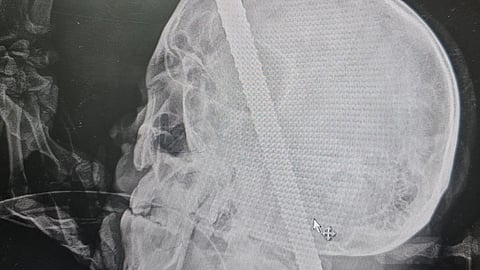

وبين التجمع الصحي بأن الفرق الطبية قدمت الإسعافات اللازمة والاستعانة فوراً بفريق من الدفاع المدني لقطع جزء من الجسم المعدني وإكمال الفحوصات الطبية والأشعة المقطعية، والتي أظهرت مسار الجسم المعدني ومروره في أماكن معقدة وذات خطورة عالية على حياة المستفيد.

وأوضح تجمع المدينة المنورة الصحي أن المستفيد وصل إلى طوارئ المستشفى الرئيسي بمدينة الملك سلمان الطبية وهو في حالة حرجة فاقداً للبصر في عينه اليسرى، بالإضافة لنزيف حاد وآلام شديدة نتيجة اختراق جسم حديدي بطول 43 سم وعرض 14 ملم لتجويف العين اليسرى والفك العلوي، مرورًا بقاع الجمجمة والفقرة العنقية الأولى وقناة الحبل الشوكي، حتى وصوله للجزء الخلفي من الفقرات العنقية.